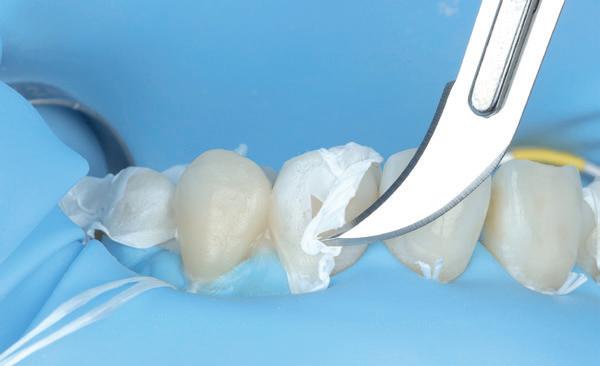

Nadat de vaste apparatuur verwijderd is (afbeelding 7 en 8), zie ik mevrouw voor het maken van een afdruk/scan ten behoeve van een wax-up. Aangezien ik in deze casus wil werken met de injectietechniek, is een wax-up noodzakelijk.

Voor een wax-up ten behoeve van opbouw met composiet worden strengere eisen gesteld dan aan een motivational wax-up. Wanneer je de wax-up wil gebruiken voor het overzetten met composiet, is het belangrijk om een nauwkeurige transparante mal te hebben (Exaclear, GC). Deze mal moet transparant zijn om voldoende licht van de polymerisatielamp door te laten om zeker te weten dat al de composiet goed uithardt. Verder is het belangrijk om te weten dat Exaclear een ontzettend nauwkeurig materiaal is. Dit houdt in dat je een exacte kopie zult maken van de wax-up. Alle foutjes en oneffenheden in de wax-

up zullen dus ook overgezet worden in de mond. Om de situatie van de wax-up zo goed mogelijk om te zetten in de mond is het daarnaast belangrijk dat je mal voldoende afsteuning heeft. Dit kun je doen door sommige elementen of delen daarvan niet te laten opwassen (in dit geval de palatale zijde van de elementen).

Over de wax-up heeft de tandtechnieker een puttymal gemaakt en de wax-up wordt overgezet in de mond met behulp van een bisacryl (Luxatemp Star A2, DMG) (afbeelding 9-11). Nadat de wax-up / mockup is goedgekeurd, wordt een afspraak gemaakt voor de daadwerkelijke omzetting in composiet.

ten dat de mal volledig gevuld is. Deze overmaat kan vervolgens eenvoudig verwijderd worden met een scalpel (Swann Morton 12D). (afbeelding 15)

Een nadeel van de injectietechniek is dat je vaak maar met één kleur kunt injecteren, hierdoor krijg je monochromatische restauraties. Voor veel patienten is dit geen probleem, maar soms wil je wat meer dieptewerking en effecten aanbrengen in een element. In deze gevallen kun je kiezen voor een hybride techniek waarbij je een traditionele layering strategie toepast om vervolgens de laatste (glazuur) laag te injecteren. Hiermee kopieer je exact de waxup en scheelt dat een heleboel polijsten en afwerken (vaak het moeilijkste van de behandeling). Hoe mooi deze techniek ook klinkt, het is een erg lastige techniek. Je moet er namelijk met elke laag composiet voor zorgen dat je transparante mal nog steeds past en er voldoende ruimte is voor je glazuurlaag (0.3 - 0.5mm). Daarnaast hebben we in deze casus ook nog te maken met diastemen. Diastemen zijn per definitie eigenlijk niet te sluiten met alleen de injectietechniek. De transparante mal is onvoldoende in staat om een mooie cervicale aansluiting te krijgen van de restauratie op het element. De diastemen zullen dus vaak (gedeeltelijk) met de hand moeten worden gesloten alvorens de rest te injecteren.

De puttymal wordt gepast (afbeelding 16) en gebruikt om de incisale randen van de 13 en 23 te herstellen. Hiervoor wordt gebruikgemaakt van G’aenial A’chord JE (afbeelding 17). Vervolgens moet het diasteem bij de 13 (afbeelding 18) met de hand verkleind worden om dit element te kunnen injecteren. Eerst wordt een dentine laag (G’aenial A’chord A2, GC) aangebracht om de tussenruimte tussen de incisale rand en het element op te vullen (afbeelding 19). Daarna wordt een doorzichtig stripje aangebracht om de 13 mesiaal uit te kunnen bouwen (afbeelding 20). Met behulp van wat composiet (G’aenial A’chord A2, GC) wordt het diasteem verkleind. Op de wax-up wordt gemeten hoe breed element 13 in de wax-up is en vervolgens wordt de contour zo teruggeslepen (Optidisc, Kerr) tot de juiste breedte is bereikt (afbeelding 21). Dezelfde stappen worden doorlopen bij element 23 en de mal wordt opnieuw gepast (afbeelding 22). Nadat geverifieerd is dat de mal goed past, worden de buurelementen afgedekt met teflon tape (afbeelding 23) en worden elementen 13 en 23 geïnjecteerd. Wederom streven we naar een beetje overmaat om zeker te weten dat het element volledig is opgevuld met composiet en er geen luchtbellen aanwezig zijn (afbeelding 24). De overmaat wordt wederom ver-

wijderd met een scalpel (afbeelding 25) en de puttymal wordt opnieuw gepast (afbeelding 26). Eventuele interferenties die zijn ontstaan na het injecteren van de 13 en 23 worden verwijderd om ervoor te zorgen dat de puttymal weer goed op zijn plek komt.